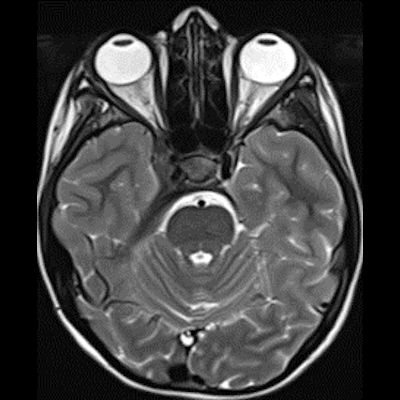

14 yaş, K

Baş ağrısı ve sağda abdusens felci

Neurosarcoidosis manifesting as cavernous sinus syndrome in systemic sarcoidosis

Sağ kavernoz sinüste kontrastlanan ICA yı çevreleyen daraltan yumuşak doku değerleri mevcuttur.Sağ parahiler bölgede lenfadenopati veya kitle lezyonu ile uyumlu olabilecek görünüm mevcuttur.Ayırıcı tanıda Nazofarink Ca metastazı,lenfoma,sarkaidoz,wegener granulomatozu düşünüle bilir.Çocuk hasta olduğu için daha çok lenfoma olarak düşündüm